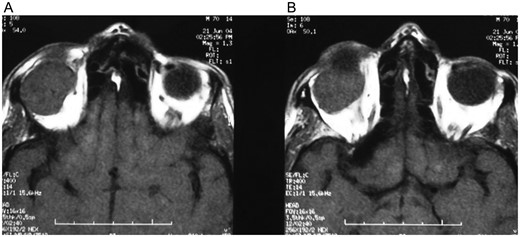

A 62-year-old male patient referred to our clinic due to painless exophthalmia of his right eye for the last 2 years. On neurological examination of the patient, there was no abnormality except for the up-gaze restriction and severe exophthalmia. Computerized tomography revealed an intraorbital mass in the right eye. A well-defined 2.5-cm isodense mass was located on the right lacrimal gland. The mass was contrasted homogenously (Fig. 1a and b). Cranial magnetic resonance imaging (MRI) revealed an isointense mass on the superolateral part of right orbita in the coronal intersections and it was contrasted homogenously (Fig. 2a and b). The existing score of our patient according to Rose and Wright was +8 points. Combined orbitofrontal craniotomy was performed through a transcranial approach. The well-defined, soft, white, 2.5-cm mass was removed completely. Exophthalmoses disappeared after the surgery (Fig. 3a and b). Histological examination of the surgical specimen covered the epithelial and stromal components that formed the glandular structures. Keratinized plugs were seen in some glandular lumens. Cartilaginous differentiation of stroma was found (Fig. 4a–d). Based on these findings, the tumor was diagnosed as pleomorphic adenoma. There was no recurrence after 8-year clinical follow-up.

(A and B) Cranial MRI revealed a homogenously contrasted mass on the superolateral part of the right orbita.